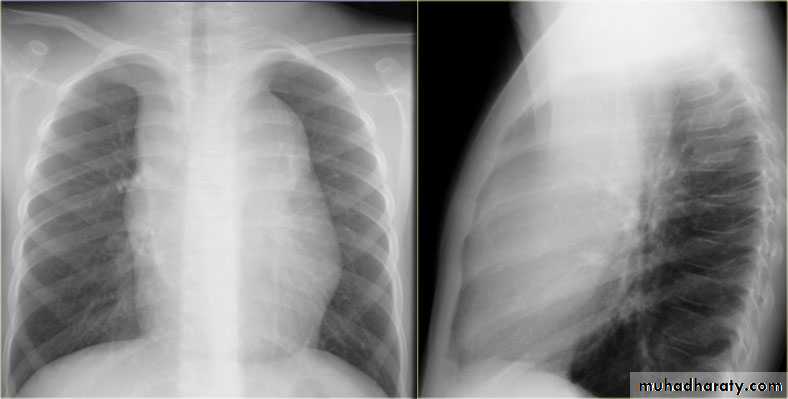

32.RT ML consolidation ( PA & lat. view )

33.RT ML consolidation (Lat. view )

34.LUL consolidation (PA & Lat. View )

35.LT.lower lobe consolidation ( PA & Lat. view )